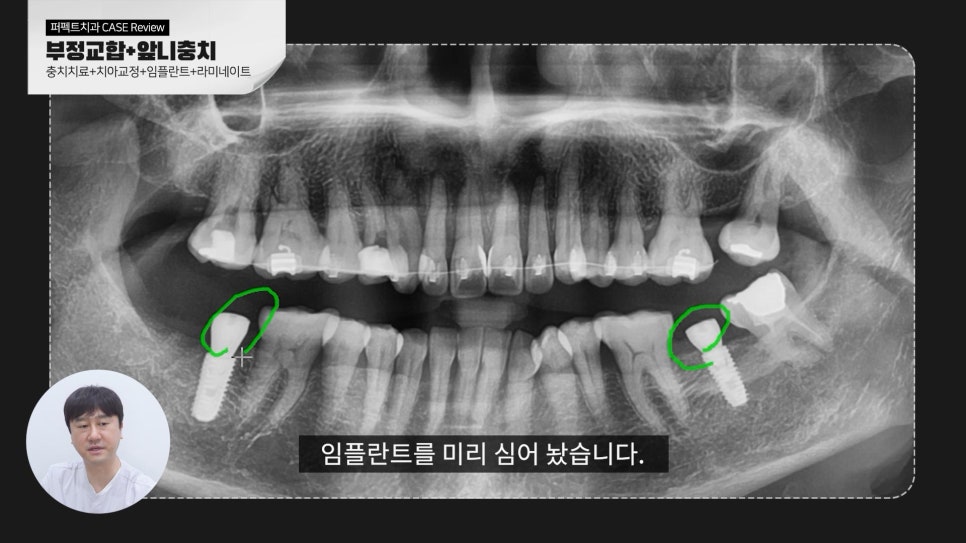

파노라마 사진을 보시면 아래쪽 뼈가 더 손실되기 전에 임플란트를 먼저 식립하였고 교정이 진행중이기 때문에

처음보다 어느정도 치아가 펴져있는 단계입니다.